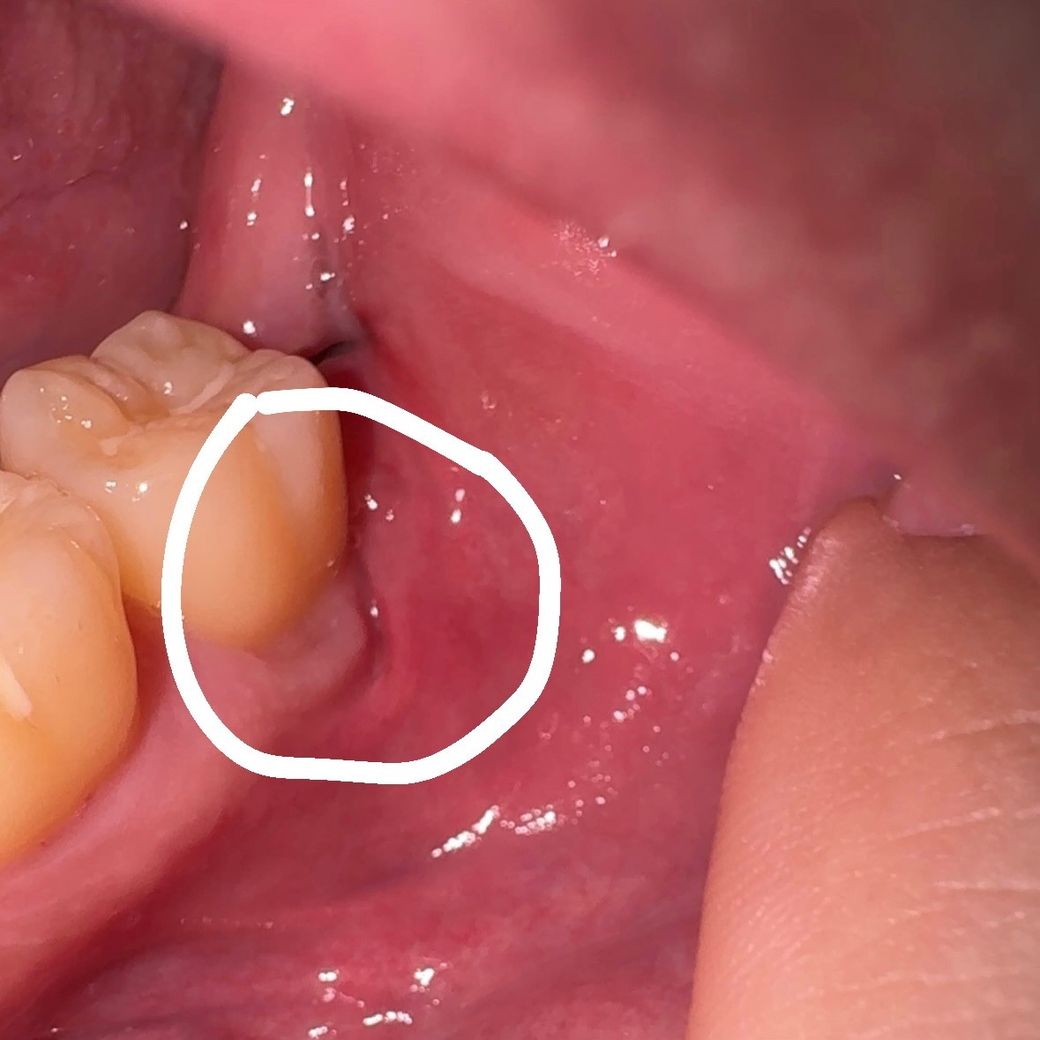

아래 매복 사랑니 발치 후 10일 정도 지났는데 저렇게 벌어지는 잇몸을 발견했습니다. 봉합을 안한걸까요? 병원에 다시 가봐야하는지 의문입니다.

아래 매복 사랑니 발치 후 10일 정도 지났는데 저렇게 벌어지는 잇몸을 발견했습니다

잇몸에 층이 나뉘어서 그렇지 잇몸이 벌어진 양상은 아닌 것으로 사진상 보입니다. 사랑니 발치 부위 잇몸 치유 과정에서 저렇게 잇몸 모양이 형성된 것 같습니다. 큰 문제는 없어 보입니다.